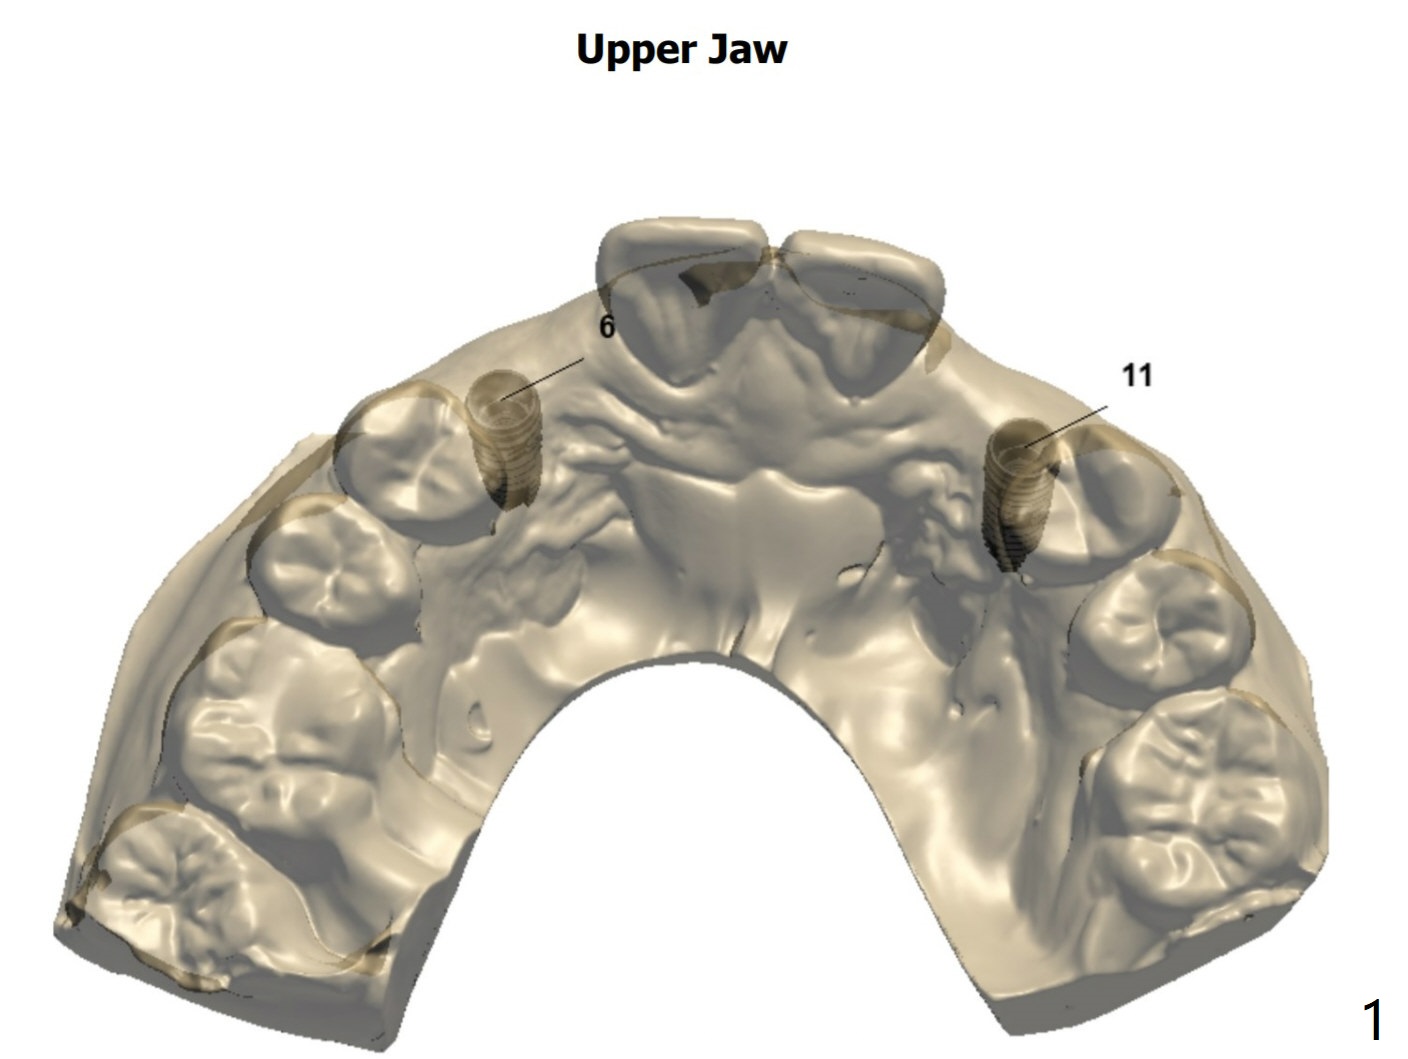

侧植骨

两个PRF膜,两个骨块

Return to No Deviation 尖牙即种 Oral Scanner